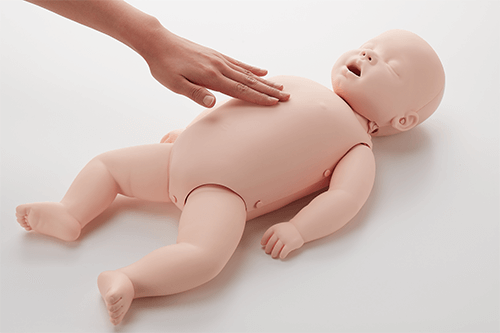

- The non-toxic materials are soft and smooth to represent an infant’s skin.

- Brayden Baby allows the correct compression depth of at least a 1/3rd of the AP distance of manikin (4cm).